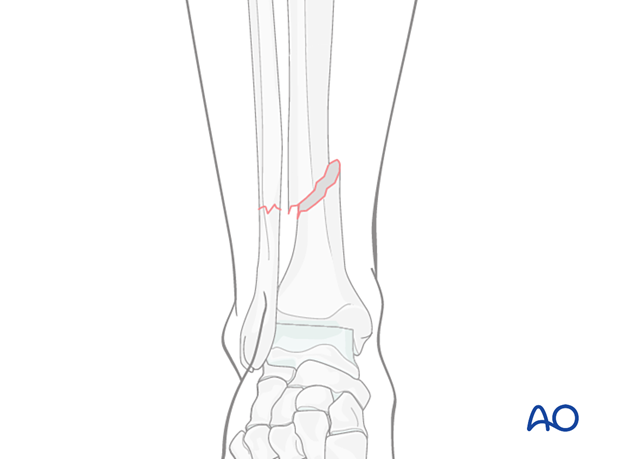

Compression plating can be used for any simple oblique tibial fracture.

It is especially useful for the treatment of fractures in children with open growth plates, where significant displacement is present, and anatomical reduction is indicated.

Case example of an oblique tibial shaft fracture